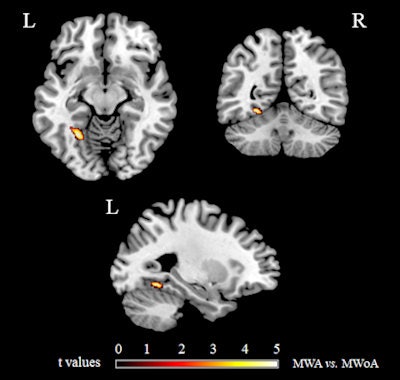

Areas showing significant GM volume differences (p < 0.05, familywise error corrected) between migraine patients with (MWA) and without (MWoA) aura, superimposed on a high-resolution T1-weighted template. MWA vs. MWoA: GM volume increase of the left fusiform gyrus.There were not any significant white-matter changes in migraine patients compared with nonmigraine patients, nor was there a correlation between gray-matter abnormalities and disease duration or attack frequency.

Areas showing significant gray-matter (GM) volume differences (p < 0.001, uncorrected) between migraine patients and healthy controls, superimposed on a high-resolution T1-weighted template. Areas with reduced gray-matter volume in migraine patients versus controls are shown in blue; areas with increased gray-matter volume in migraine patients versus controls are shown in red. All images courtesy of Dr. Massimo Filippi.In other findings, the researchers found migraine patients with aura had significantly higher gray-matter volume in the left fusiform gyrus than those without aura.